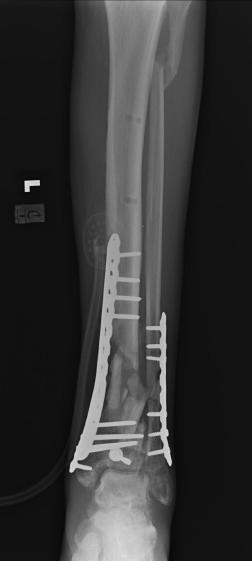

Post-corrective surgery X-Rays of the damaged right & left legs / ankles

The first two x-rays show Liam’s left ankle and pelvis prior to the accident. For comparison purposes it is interesting to see the

differences. The next x-rays were taken after the corrective surgery performed by Dr. Armendariz. Noticed that Dr. Armendariz has used tibia

bracing and also aligned the bone fragments of the left leg so that they could heal in the proper orientation. The external fixation has been

removed and Liam’s left foot has been returned to a more natural alignment.